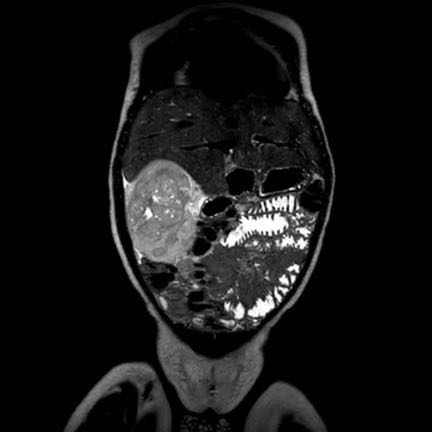

Ca lâm sàng 1

Hình ảnh chuỗi xung T2W mặt phẳng coronal cho thấy một khối u không đồng nhất ở thận trái với các thành phần nang nhỏ.

Khối u ngấm thuốc kém hơn so với phần nhu mô thận bình thường còn lại ở ngoại vi.

Các thành phần đặc của khối u cho thấy hạn chế khuếch tán rõ rệt (mũi tên).

Đây là u Wilms ở bé trai năm tuổi. Hóa trị tiền phẫu được thực hiện theo phác đồ Umbrella của SIOP-RTSG, sau đó tiến hành cắt thận.